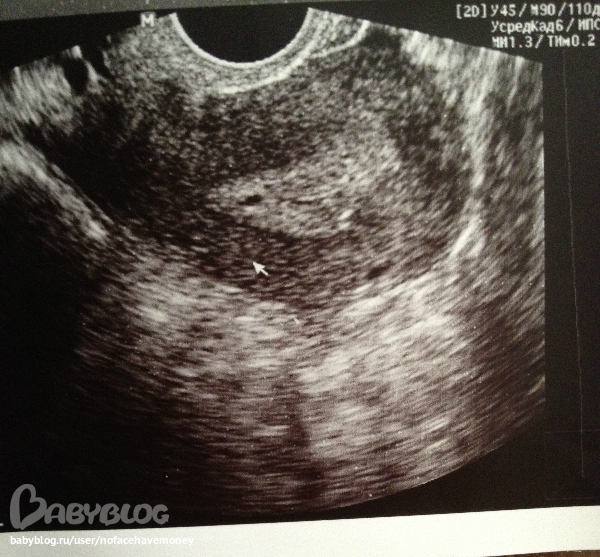

вот смотрите девочки! я пошла на узи на 4 день задержки) знаю что рано.. посмотрели на узи и сказали плодное яйцо 0,2 см ,

вот смотрите сами:

гинеколог посмотрела сказала матка увеличенная, бер-ть развивающаяся..

эндометрий толщиной в 1,2 см, лоцируется анэхогенное включение d-0,2 см плодное яйцо

правый яичник 3,2 * 2,7 см эхоструктура мелкофолликулярная

левый яичник- 3,4*2,4 эхоструктура -лочируется анэхогенная полость с эхопризнаками желтого тела d- 1,6 см

матка:длина тела 4,9 см

толщина тела 3,9 см

всё это было 9 сентября...